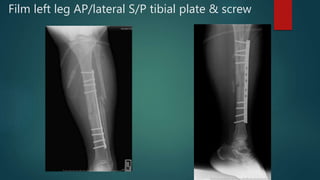

Film left leg AP/lateral S/P tibial plate & screw

Film left legAP/lateral S/P tibial plate & screw